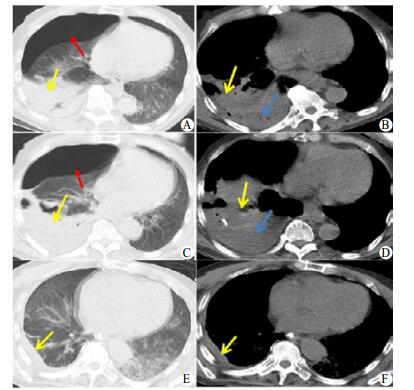

患者,男性,73岁,因“突发左侧肢体功能障碍伴言语不清3 h”于2017年12月16日入住神经外科,结合CT(图 1A 、B )诊断为:右侧基底节脑出血,左下肺炎症。患者饮水试验阳性,为行肠内营养,予留置鼻胃管,过程顺利,上腹闻及气过水声后间断推注150 mL食糜,后出现呛咳,呼吸困难。经家属要求后拨除胃管,胃管尖端可见明显血迹。胸部CT提示右侧气胸(压缩60%),右肺下叶感染,胸腔积液。考虑胃管误入肺引起液气胸。予胸腔闭式引流及抗感染治疗,10 d后因反复高热、呼吸困难及氧合下降转入ICU。查体:T 39.8℃,P 114次/min,R 35次/min,BP 195/104 mmHg(1mmHg=0.133kPa),SPO2 89%(储氧面罩),GCS评分为7分(2+2+3),点头样呼吸,右下肺闻及明显痰鸣音及湿啰音。右侧胸腔闭式引流管大量气泡溢出及少量黄色胸水。胸水常规:深黄混浊,白细胞4+/HP,蛋白定性阳性。胸水生化:总蛋白45.4 g/L,白蛋白25.2 g/L,LDH 10 305 U/L(50~250 U/L),CRP 65.8 mg/L(0~8 mg/L)。胸水涂片见革兰阴性(G-)杆菌。血常规WBC 22.81×109/L(4.0~10×109/L),N 94.2%(50%~70%); 血CRP 176.06 mg/L(0~8 mg/L),降钙素原1.12 ng/mL(0~0.25 ng/mL)。血气分析:pH 7.25,PaO2 53.7 mmHg,PaCO2 42.7 mmHg,SaO2 81.6%,血乳酸2.6 mmol/L。复查胸部CT示:右肺压缩60%,胸腔积液较前增多(图C、D)。诊断:右侧气胸合并脓胸,Ⅰ型呼吸衰竭。予气管插管,机械通气,B超引导下反复多点穿刺抽脓,并改粗管引流,胸腔冲洗,亚胺培南/西司他丁钠(泰能)联合利奈唑胺(斯沃)抗感染,鼻肠管肠内营养支持。患者入ICU第48天脱机成功。复查胸部CT气胸完全吸收,感染灶明显吸收好转(图E、F),后转普通病房。

| 入院2 d:右肺压缩约60%(红色箭头所指为气胸),右肺下叶感染灶(黄色箭头所指为感染灶),右侧少量胸腔积液(蓝色箭头所指为胸水)(图A和B)。入院10 d:右肺压缩约60%(红色箭头所指为气胸),积液较前明显增多(蓝色箭头所指为胸水)(图C和D)。入ICU 48 d:气胸吸收,感染灶明显吸收好转(图E和F,箭头所指为感染灶) 图 1 胸部CT动态变化 |